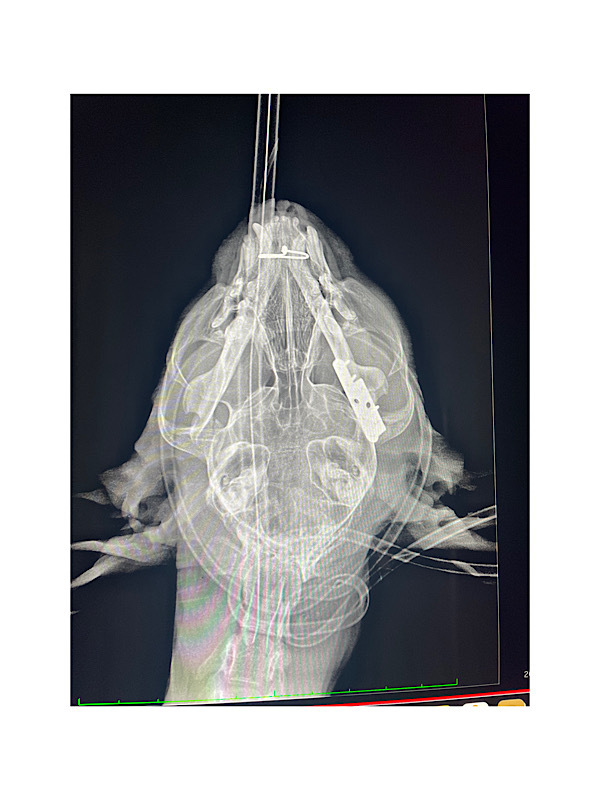

↑手術後のレントゲンです。

※神経がたくさん通ってる場所なので難しい手術だったそうです。